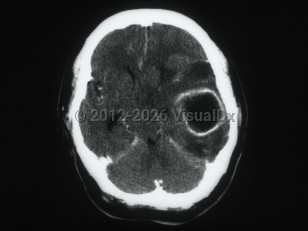

Epidural intracranial hematomaEpidural intracranial hematoma